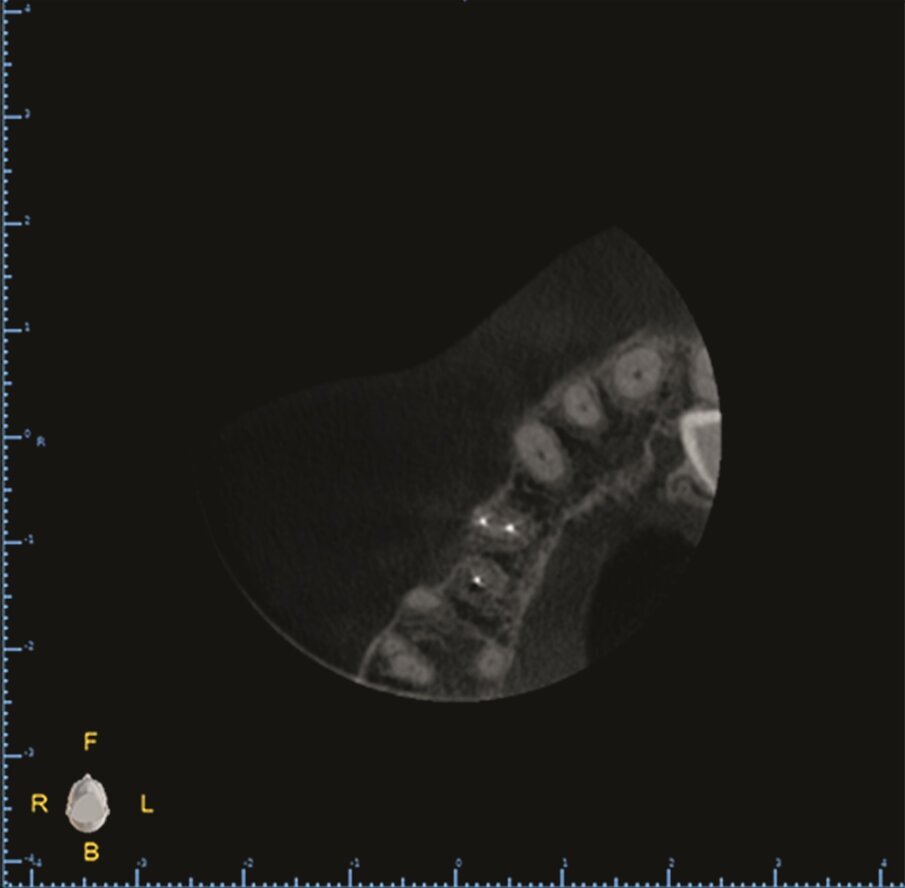

At the two-year follow-up, clinical examination and CBCT showed evidence of healing of the apical lesions and the cortical bone without symptoms or complications (Figs. 1l–n).

Fig. 1l–n: Two-year follow-up CBCT scan, axial (l), …

… and sagittal views (n).